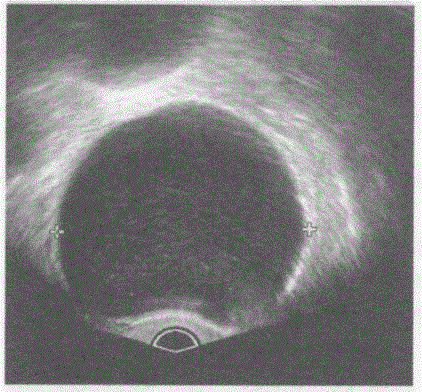

问题 临床资料:女,57岁,自述下腹部进行性增大不适半年余。妇科内诊:左附件区触及拳头大肿物。 超声综合描述:经阴道扫查左附件区可见8.0cm×6.1cm无回声区,边界清晰,形态规则,内见少许分隔,CDFI:无回声周边可见条样血流信号。见下图及彩图。 {图1} 超声提示:

选项 A.左卵巢畸胎瘤 B.左卵巢囊肿(黏液性囊腺瘤) C.左卵巢黄体囊肿 D.左卵巢黄素囊肿

答案 B